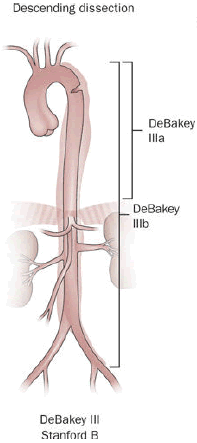

Aortic Dissection

Aortic dissection is caused by shearing force allowing blood leaking through the media of the aortic wall due to an intimal tear.

Aortic dissection occurs in the high-stress zone of the proximal portion of the aorta and is accompanied by medial weakening.

Risk factors of aortic dissection include:

- Hypertension in elderly persons, characterized by vasa vasorum hyaline arteriosclerosis

- Genetic connective tissue abnormalities in younger individuals such as Marfan syndrome or Ehlers-Danlos syndrome, characterized by weak connective tissue and cystic medial degeneration

The media sags as a result of decreased flow.

Weakness of the connective tissue in the media is a characteristic symptom of Marfan syndrome and Ehlers-Danlos syndrome (cystic medial necrosis).

Symptoms of aortic dissection include:

- Intense chest pain

- Chest pain that radiates to the back

Complications of aortic dissection include:

- Death secondary to cardiac tamponade (the most common)

- Rupture with lethal hemorrhage

- Obstruction of branching arteries (such as the coronary or renal arteries)

- End-organ ischemia